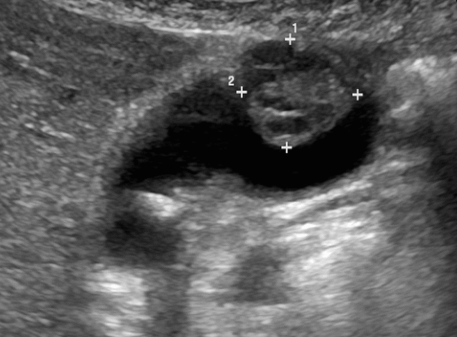

1. Polyp type (용종형)

가장 흔한 타입으로 내부에코가 밝고 균일한 용종모양이다. 또한 조직학적으로 잘 분화된 암이며, 종괴의 크기가 1cm 이상이면 의심할 수 있다.